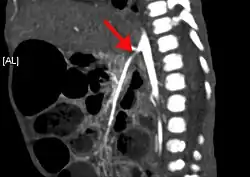

Enhanced computed tomography showing severe atherosclerosis of the arteries. The aorta shows broad calcifications, and the celiac artery shows moderate stenosis, although the lumen of the superior mesenteric artery was relatively patent. In addition, stenosis of the inferior mesenteric artery was very severe.

Abdominal angina is caused by obstruction or stenosis of the inferior mesenteric artery (IMA), celiac trunk, or superior mesenteric artery (SMA).[4] More than 95% of abdominal angina is caused by stenosis of the splanchnic arteries due to local atherosclerosis.[5][6] The occlusion mainly affects the ostia or the last few centimetres of the mesenteric arteries.[7]